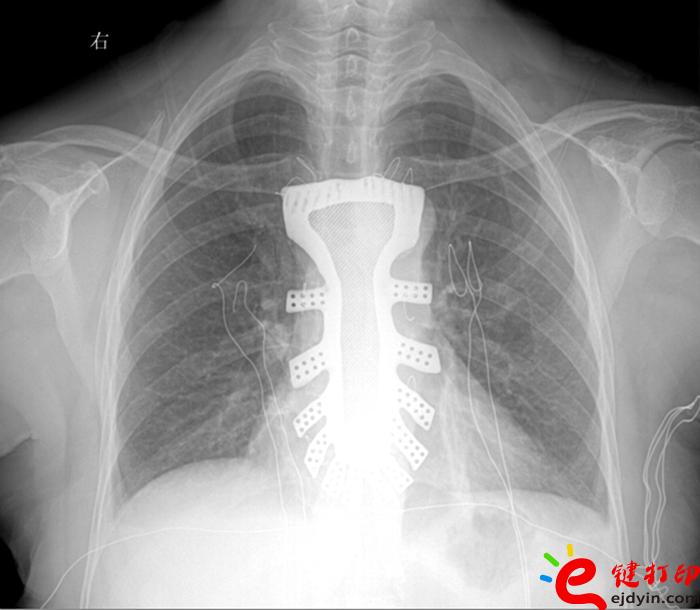

當然,“3D打印”的世界遠不止如此。據(jù)參加大會的專家和企業(yè)負責人介紹,目前“3D打印”已被運用在文化創(chuàng)意、文物修復(fù)、生物醫(yī)療、工業(yè)設(shè)計等多個領(lǐng)域。如,在航空航天器材上,一些關(guān)鍵零部件采用“3D打印”一次成型,使得其功能更加實用,重量大幅減少;在醫(yī)療領(lǐng)域,“3D打印”被運用于牙齒再造和骨骼修復(fù)等方面,從而使治療更加精準。